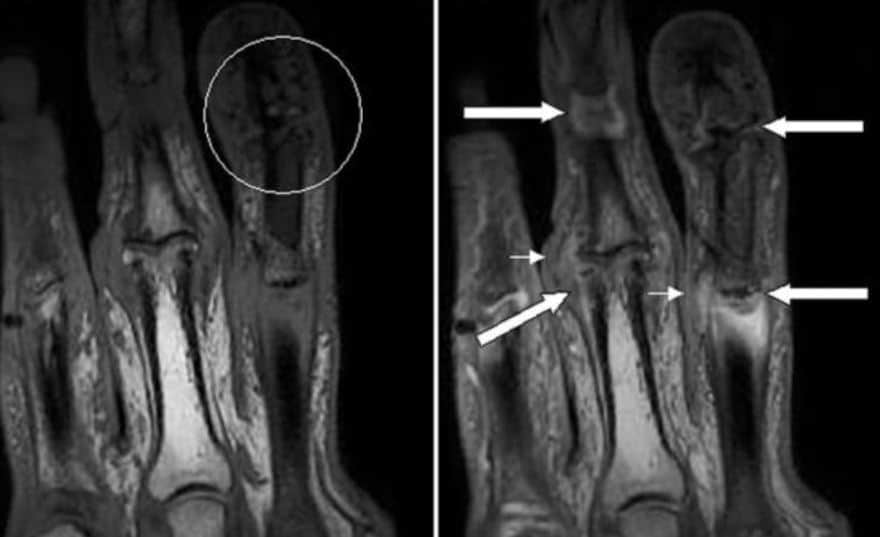

Инструментальные данные

Помощь в постановке диагноза оказывает такой инструментальный метод обследования как рентген.

Рентгенологическое исследование: чаще выполняют снимки суставов стоп, кистей, сакроилеальной области и грудино-ключичного сочленения.

В данных областях на плёнке могут визуализироваться остеолизис со смещениями костей в разных осях, периостальные изменения, признаки кальцификации.

Дополнительными методами могут служить УЗИ, МРТ суставов.